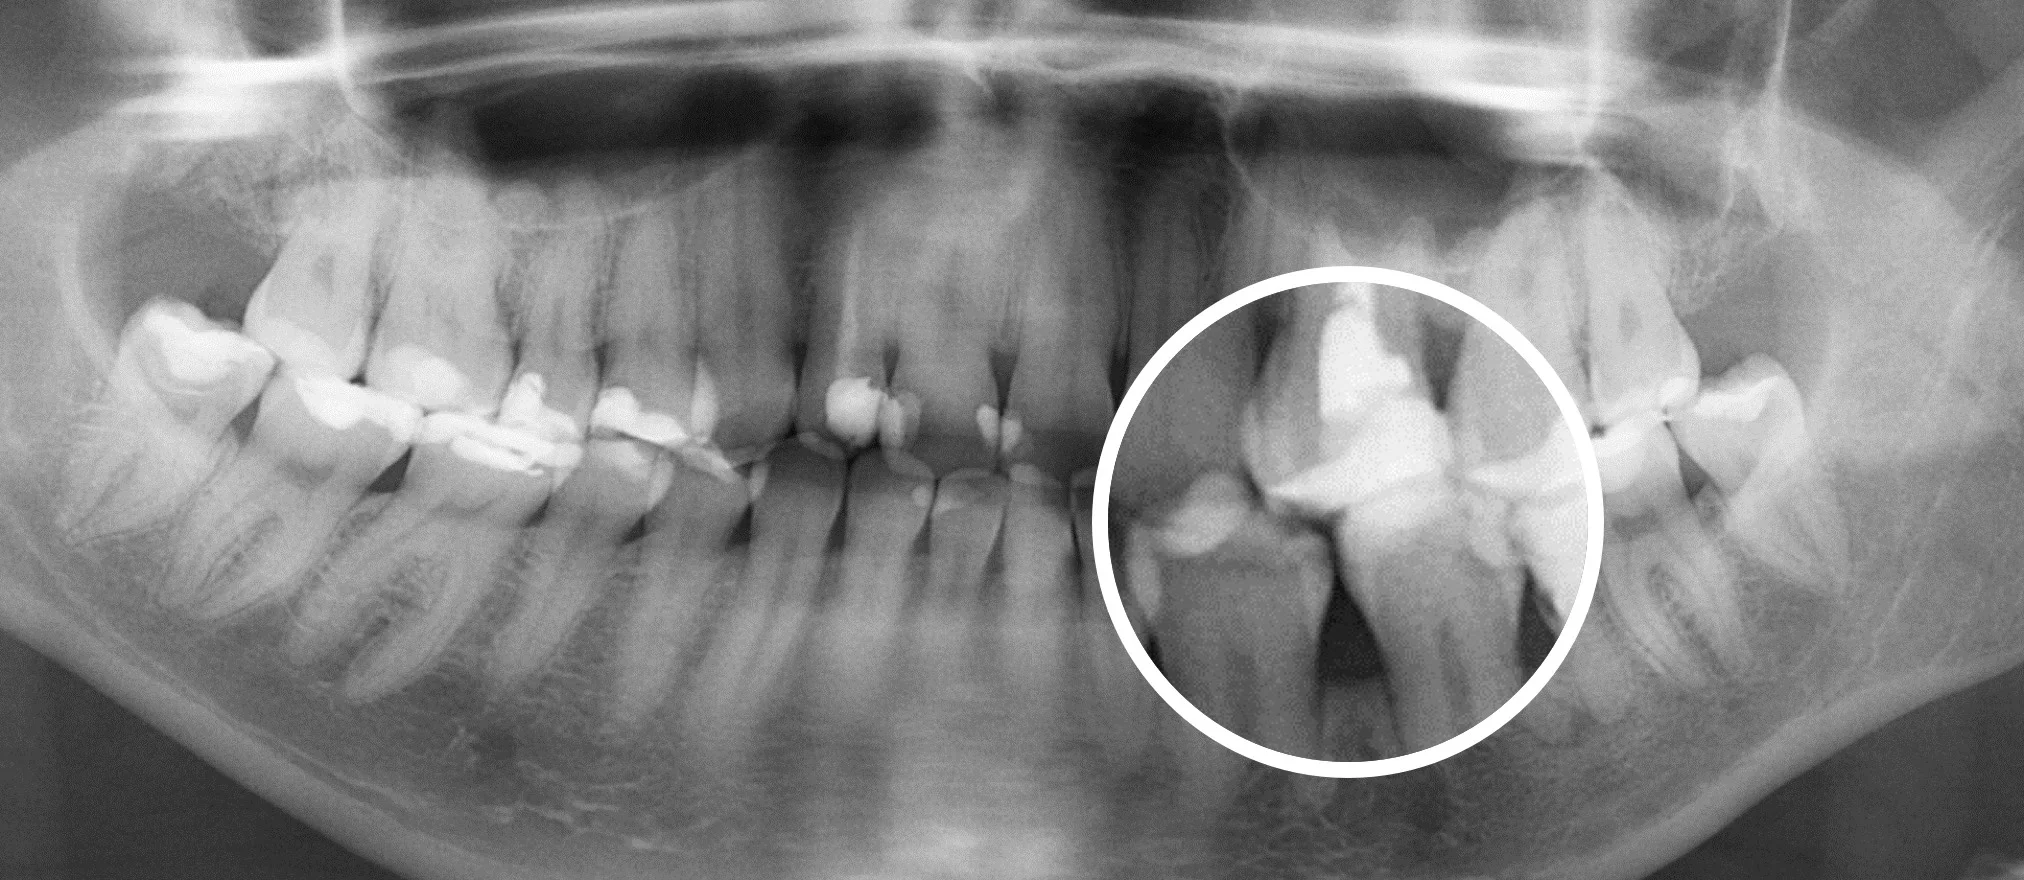

Еще 10 лет назад для того, чтобы провести диагностику зубов стоматологи использовали прицельные R-снимки и ОПГ снимки. Это снимки, которые делаются в 2D формате. Единственное, что врач мог делать с данным снимком, это приближать и удалять изображение.

На смену 2D снимкам пришли КТ снимки (компьютерная томография], которые в обиходе называют 3D снимками —новый уровень диагностики.

Сравнение 2D и 3D снимков